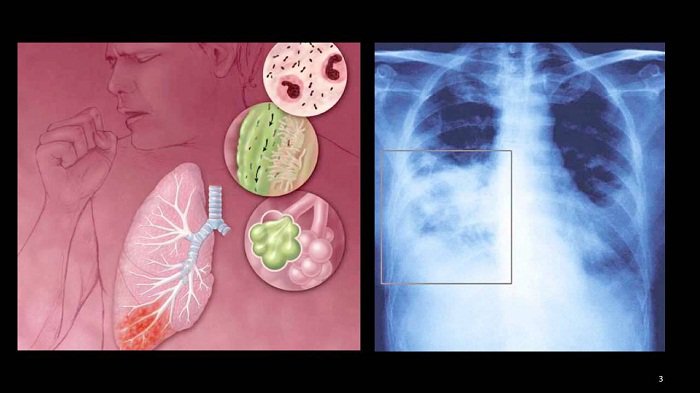

Virus RSV - Nguyên nhân gây bệnh viêm phổi ở trẻ em

06/11/2023 (GMT+7)

Virus RSV (virus hợp bào hô hấp) là một trong những nguyên nhân thường gặp gây bệnh đường hô hấp (viêm tiểu phế quản, viêm phổi) ở trẻ em. Hiện chưa có vắc-xin phòng ngừa virus RSV và thuốc điều trị đặc hiệu nên việc phát hiện bệnh sớm để có kế hoạch điều trị và chăm sóc kịp thời là rất quan trọng.